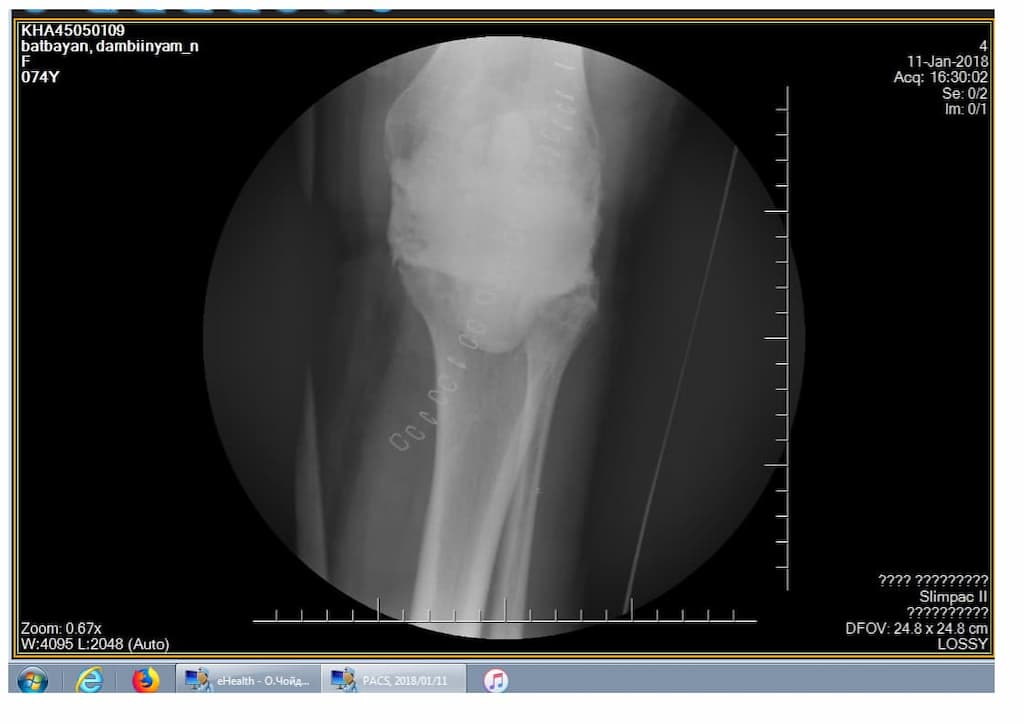

Үе дайрсан ясны анхдагч хавдар, ясны дутмагшлын үед хийгдэх мэс засалimg27Үе дайрсан ясны анхдагч хавдар, ясны дутмагшлын үед хийгдэх мэс засалimg28

Зураг 1. Сэргээн засах мэс заслын өмнөх рентген зураг. Эгц урд, хажуугаас авсан байдал. Халдварын бус шалтгаант хиймэл үений ховхрол.